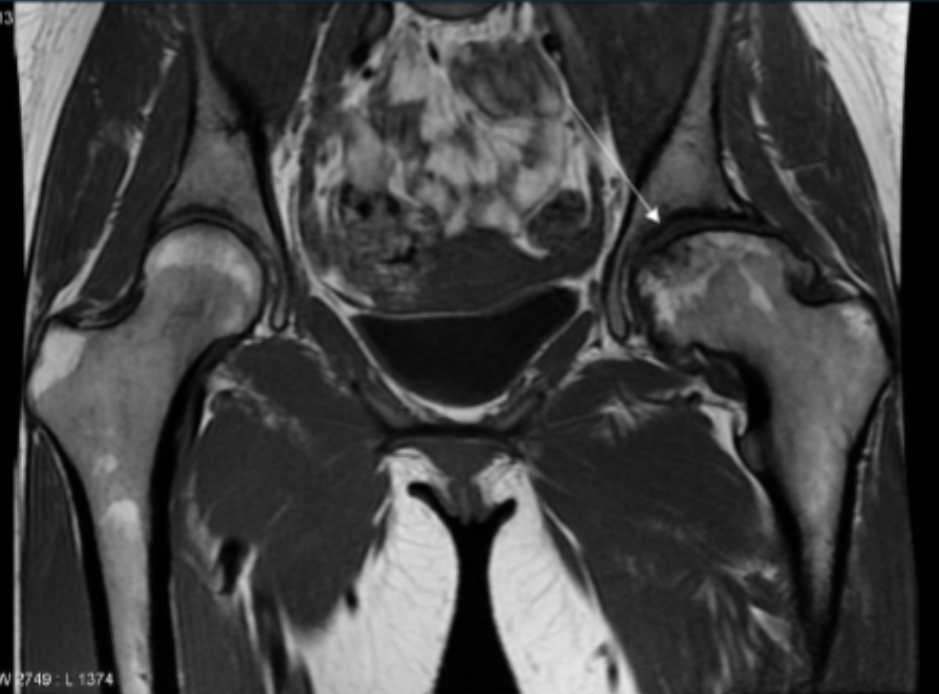

Describe the pathology indicated by the arrow (Cor T1).

AVN

Describe the pathology indicated by the arrow (Cor T2 STIR pelvis).

Trochanteric bursitis